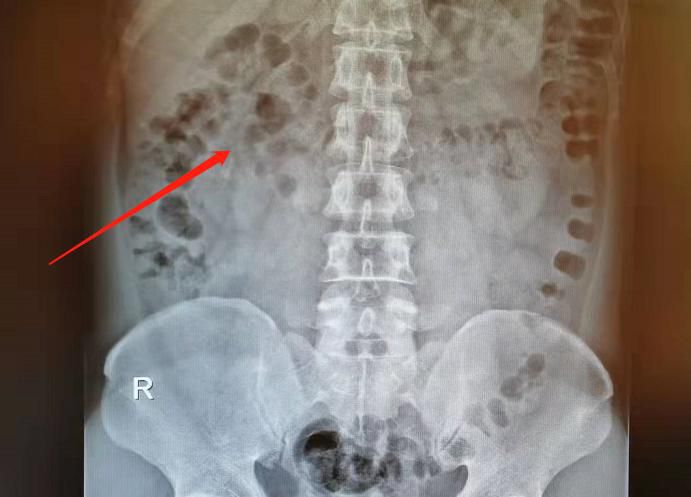

△體外碎石後。